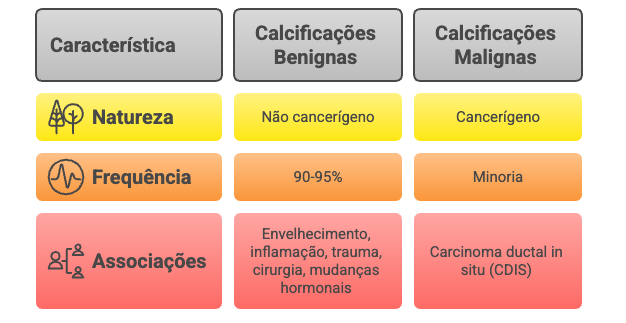

Vamos direto à questão que mais angustia: não, calcificações não são câncer. Elas são um sinal que o radiologista identifica no exame de imagem, e não células cancerígenas. Pense nelas como uma “pista” que o tecido mamário nos dá de que algo aconteceu ou está acontecendo ali.

- 90-95% das calcificações são completamente benignas

- Associam-se frequentemente ao envelhecimento natural da mama

- Podem surgir após inflamações, traumas ou cirurgias

- Relacionam-se com mudanças hormonais normais

Contudo, em uma minoria de casos, certos padrões de calcificação podem estar associados a uma atividade celular anormal, como o carcinoma ductal in situ (CDIS), um tipo de câncer de mama não invasivo e em estágio muito inicial.